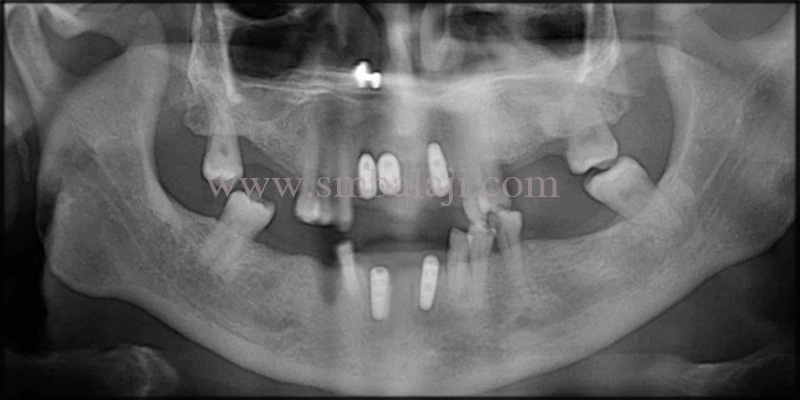

Patient returned after 6 months for implant placement. Her gums were well healed. There was no signs of pus discharge. X-ray taken affirmed no signs of pathological infection in the bone. Hence local anesthesia was administered. Renowned Implantologist, Dr.SM Balaji fixed the dental implants directly in the jaw bone, using the flapless technique.

She approached us after 3 months for the final prosthesis. Intra oral examination confirmed no pathological findings. Post-operative OPG taken, shows well osseointegrated dental implants with no signs of infection. Hence the final measurements were taken to make the fixed prosthesis. Finally, a natural looking prosthesis was fixed onto the dental implants.